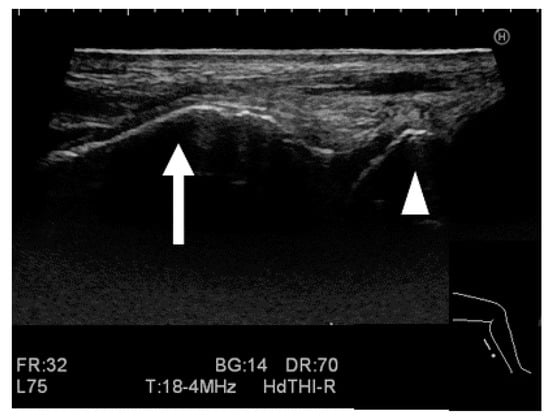

2.2.3. Ultrasound Stress Imaging Test

2.2.5. Measurement for the Stress Imaging Test